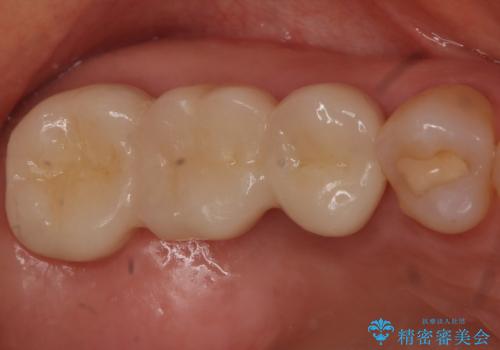

今回は抜歯後に骨の補填材を足し、適合の良いブリッジを装着していくこととなりました。

抜歯後に骨を増やしてあげることで、ブリッジと歯茎との間にすき間が生じにくくなり、適合の良いブリッジを入れることが可能となります。